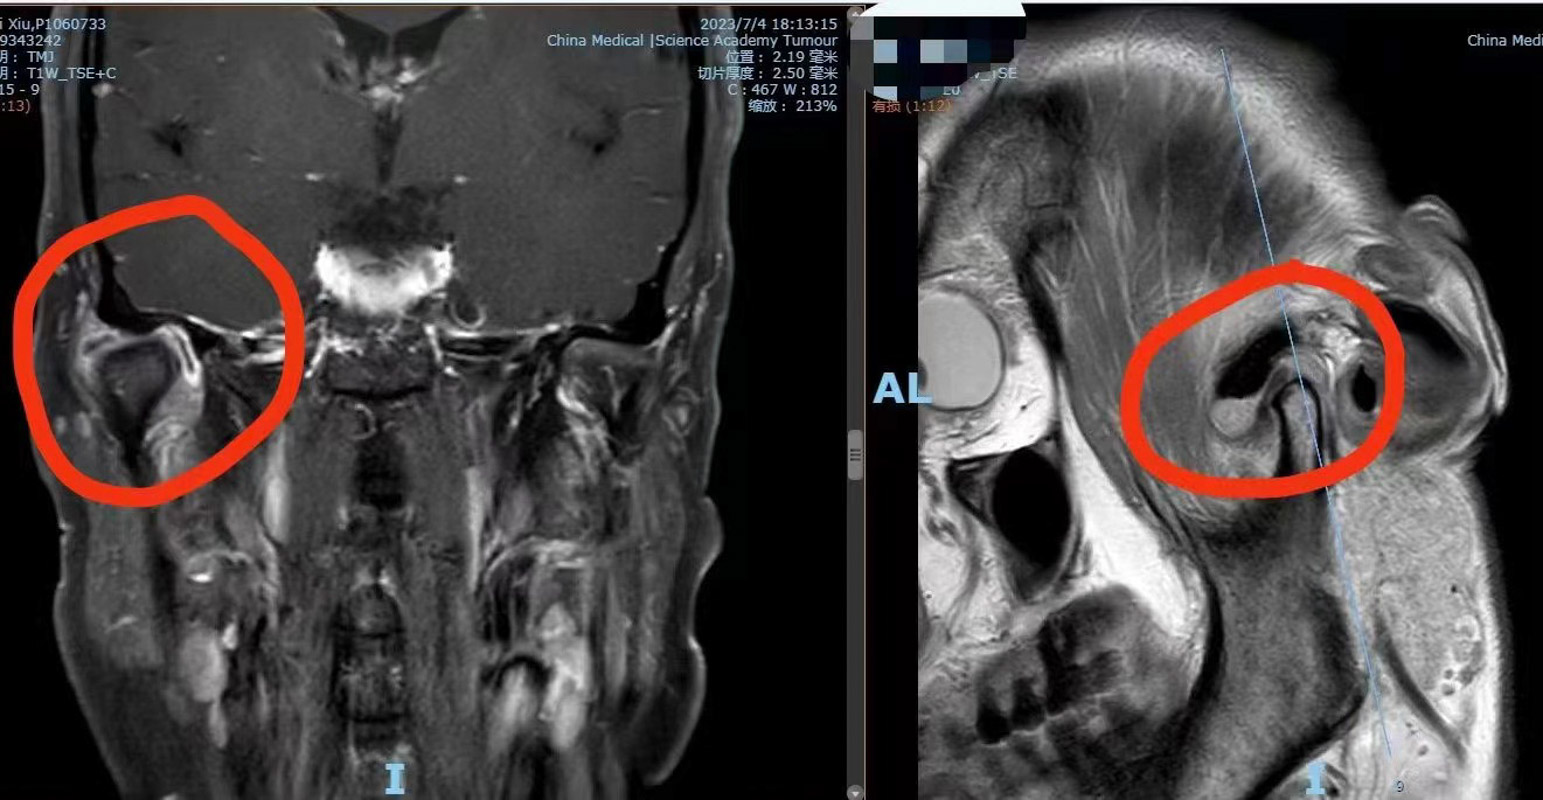

口腔科副主任醫(yī)師劉彥杰了解患者情況后,馬上安排患者進(jìn)行顳下頜關(guān)節(jié)磁共振檢查,結(jié)果顯示其右邊顳下頜關(guān)節(jié)囊擴(kuò)張,內(nèi)里有局部鈣化樣病變。“有可能是顳下關(guān)節(jié)滑膜軟骨瘤,這種疾病在顳下頜關(guān)節(jié)處十分罕見(jiàn)。”醫(yī)生根據(jù)患者情況結(jié)合多年的臨床經(jīng)驗(yàn)解釋道。

滑膜軟骨瘤是一種在膝關(guān)節(jié)比較常見(jiàn),顳下頜關(guān)節(jié)十分罕見(jiàn)的疾病。原發(fā)性滑膜骨軟骨瘤病(SynovialChondromatosis)又稱(chēng)滑膜軟骨化生(SynovialChondrometaplasia),是一種良性關(guān)節(jié)病,由滑膜軟骨化生而引起,以滑膜上形成軟骨結(jié)節(jié)為特征。這些軟骨小體多呈砂粒狀,多時(shí)可達(dá)數(shù)十個(gè),可帶蒂生長(zhǎng),向關(guān)節(jié)腔內(nèi)突出,亦可脫落進(jìn)入關(guān)節(jié)腔內(nèi),成為游離體(關(guān)節(jié)鼠),受關(guān)節(jié)滑液滋養(yǎng)而逐漸長(zhǎng)大,后期軟骨結(jié)節(jié)可發(fā)生鈣化或骨化,如“小石頭”一般,所以也稱(chēng)滑膜骨軟骨瘤病。